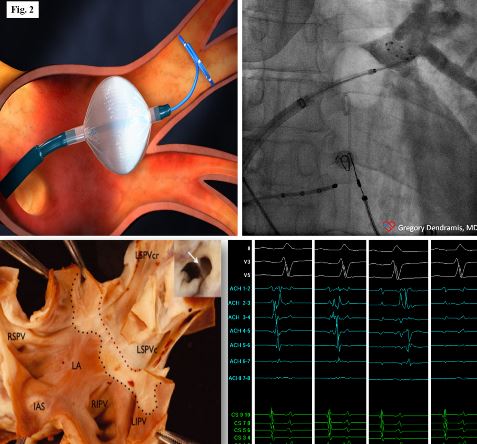

Le lesioni eseguite durante la procedura ablativa possono essere effettuate punto a punto “point-by-point” con l’ausilio di sistemi di mappaggio elettroanatomico prevalentemente mediante erogazione di radiofrequenza (fig. 1) o con metodiche a singolo colpo “one shot” con erogazione di crioenergia (fig. 2) o a breve anche con utilizzo di radiofrequenza.

Ad oggi le più utilizzate sono costituite dall’utilizzo di un catetere multielettrodo con erogazione di radiofrequenza bifasica o da un catetere con pallone che posizionato in maniera occludente a livello della vena eroga crioenergia determinando la necrosi del tessuto ed il conseguente isolamento e blocco elettrico bidirezionale delle vene polmonari aritmogene.

Figura 2